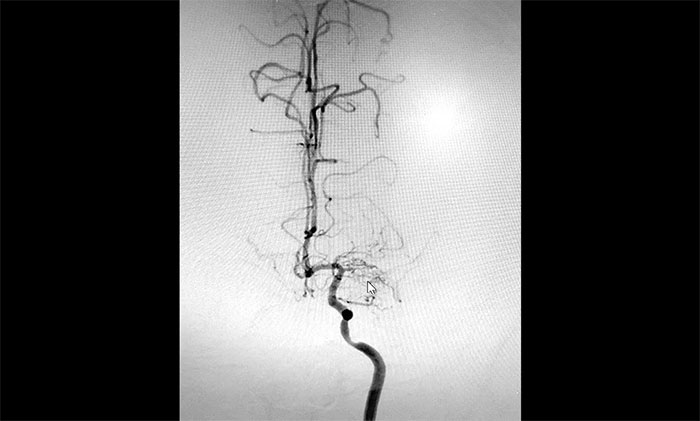

“拨开迷雾” 科学评估 定制方案

入院后,赵先生的DSA(脑血管造影)检查再次明确“烟雾病”表现:双侧大脑中动脉主干管腔纤细、分支细小;周围代偿性小血管网建立;右侧颈内动脉C3-4段纤细,显影毛糙;两侧颈内动脉C4-6段钙化形成伴管腔轻—中度狭窄。

▲DSA异常血管造影图

神经外科团队综合DSA检查结果和患者症状表现,进行了科学、审慎的评估。于耀宇主任谈到,患者双侧颈内动脉虹吸部和大脑中、前动脉主干近段明显狭窄、近乎闭塞,异常血管网形成。双侧大脑半球多发供血区灌注不足,尤以右侧缺血较为明显。